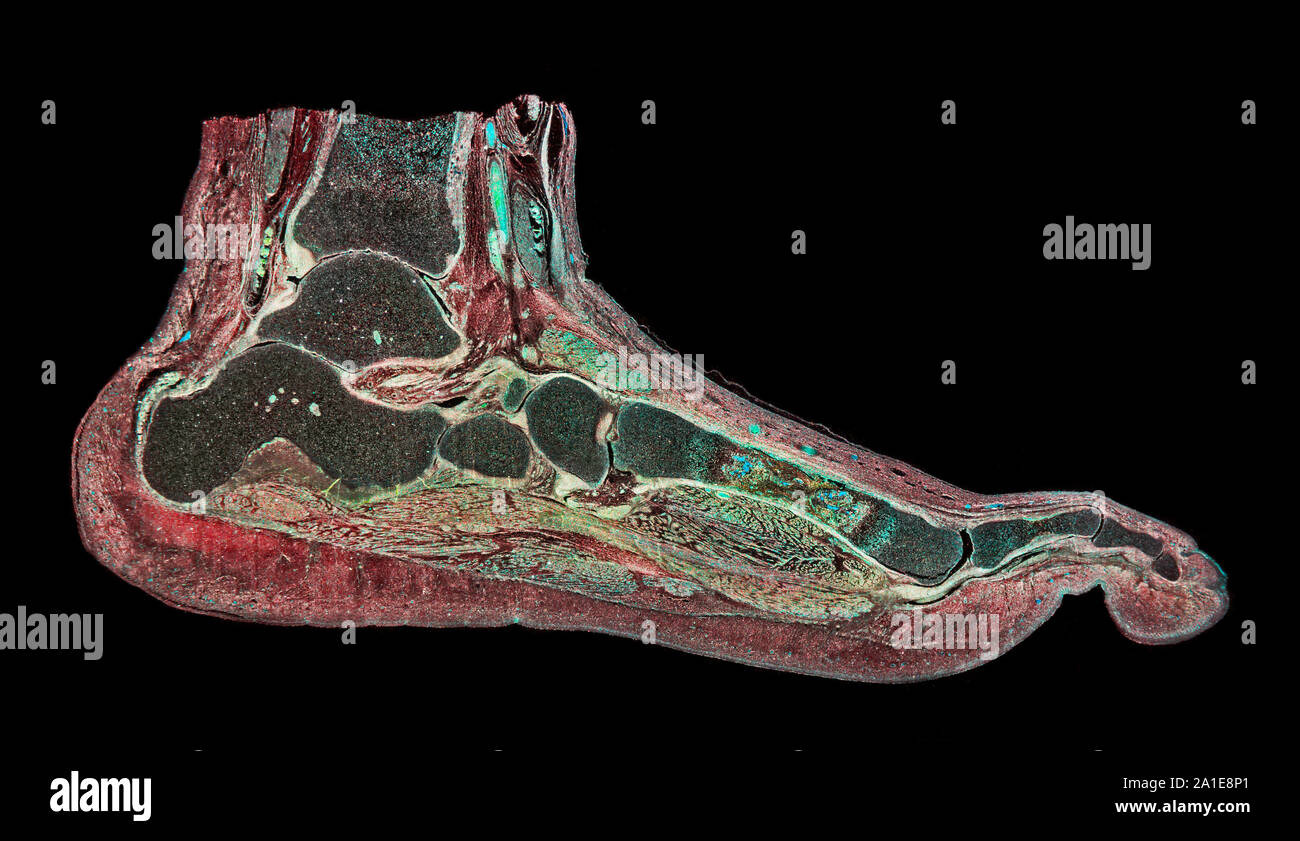

RF2ABM669–La médecine et les soins de l'illustre le tableau, les droits de l'anatomie du pied : Peau et tissus ectodermaux, os, muscles nerfs, vaisseaux sanguins